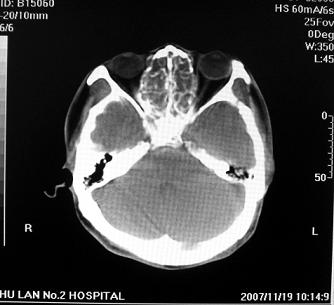

标题: CT10521:男。32岁,副鼻窦ct,请会诊。

男。32岁,鼻塞,流涕一年余。

软组织密度影填满上颌蚪 筛窦及鼻腔,并导致筛骨 上颌窦内侧壁明显骨质破坏。多考虑:内翻性乳头状瘤!

双侧鼻腔内低密度软组织影,骨壁无明显破坏,鼻腔无扩大,双侧上颌窦、筛窦软组织影,窦壁增厚,结合临床考虑鼻息肉合并慢性上颌窦炎。